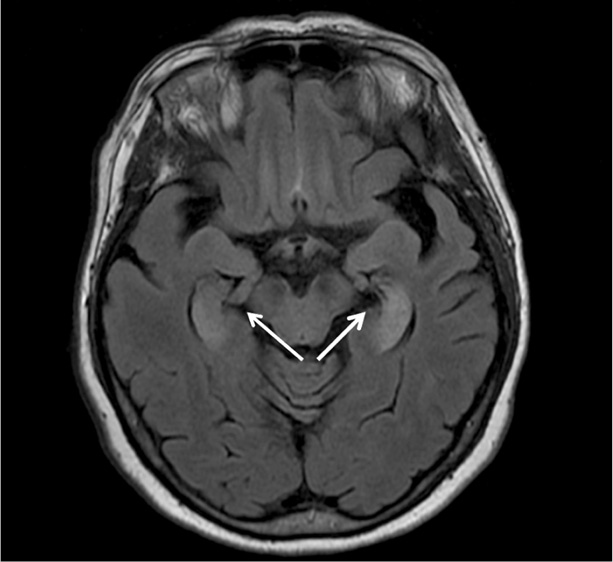

Проведена пульс-терапия метилпреднизолоном по 1000 мг внутривенно в течение 5 дней, без значимого клинического эффекта. Выполнена МРТ головного мозга в динамике после завершения пульс-терапии от 22.07.2022: МР-картина двустороннего изменения сигнала от медиальных височных структур. Выявленные изменения могут соответствовать лимбическому энцефалиту. В сравнении с предыдущим исследованием накопления контрастного препарата не наблюдается. Венозная ангиома правой лобной доли. Единичные очаги сосудистого генеза – в обоих полушариях головного мозга. Данных о наличии «свежих» ишемических изменений не получено (рис. 2).

Рис. 2. МРТ головного мозга с внутривенным контрастированием (22.07.2022). Сохраняется диффузное повышение МР-сигнала на T2 и FLAIR последовательностях в области гиппокампов с обеих сторон (МР-картина без динамики), МР-картина лимбического энцефалита – без динамики в сравнении с данными МРТ головного мозга от 13.07.2022.